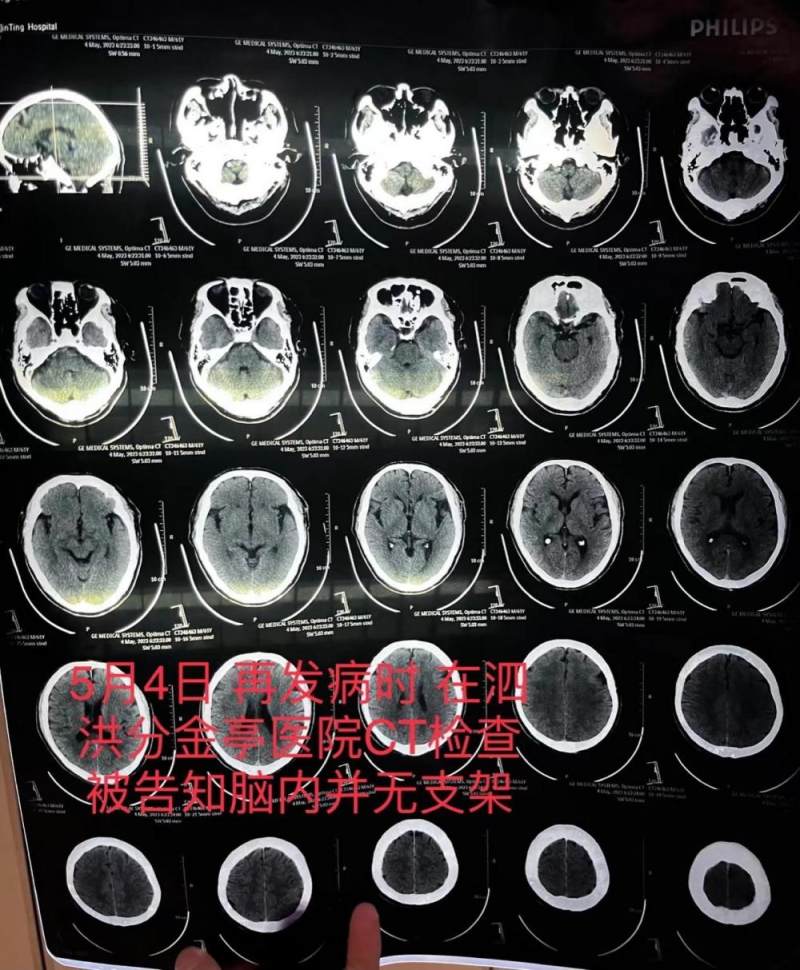

但还不到一个月,5月4日,朱老汉突发严重脑梗,被送至江苏省宿迁市泗洪县分金亭医院抢救。当时的CT血管造影显示,其颅内段部分动脉已严重堵闭,同时,并未发现植有支架。朱老汉随后被家人转入宿迁市第一人民医院,曾作为主刀医生的齐某此时承认,之前未能在患者颅内血管成功植入支架。

朱老汉在泗洪县分金亭医院的CT检查报告,显示颅内并无支架。朱先生供图